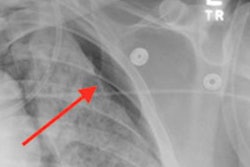

A demonstration of Critical Care Suite. Image courtesy of University Hospitals.The system has now been placed into daily clinical use, and principal investigator Dr. Amit Gupta said in a press release that the technology has helped improve workflow and patient care.